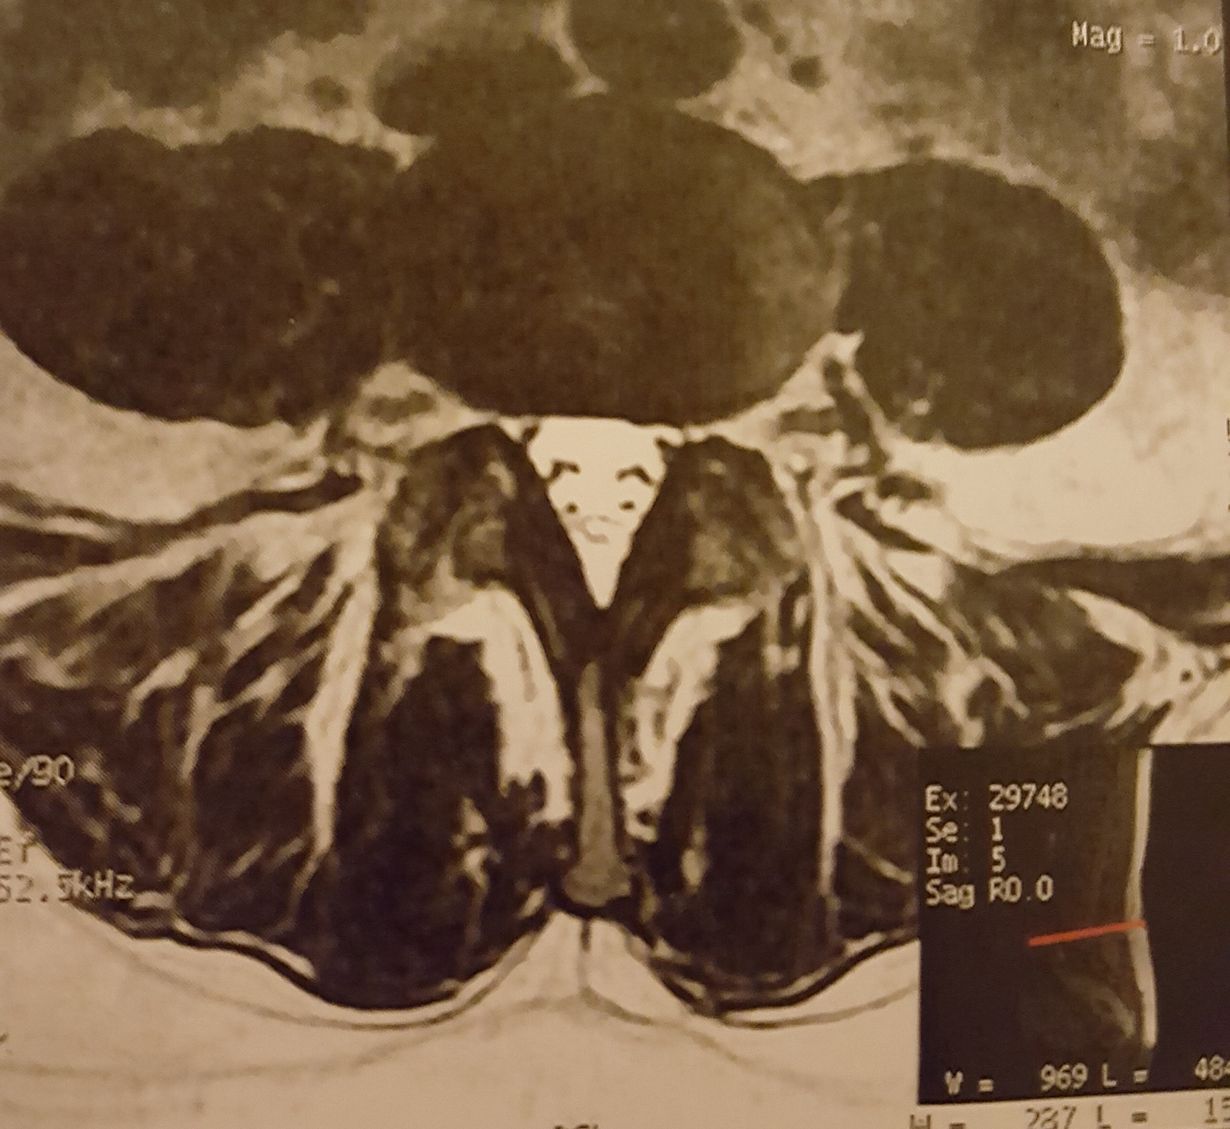

Pinokkio selässä

Koronakeväänä ennen kotikaranteenia alkoi iskias. Ei auttanut kuin sietää oikean jalan kipuilua ja tunto-oireita. Kun vihdoin toukokuussa pääsi magneettikuvaan, löytyi selästäni pitkänenäisen Pinokkion kasvot!